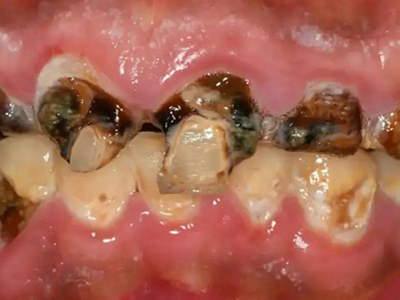

酸蚀症牙齿缺损严重有黑斑图

酸蚀症严重时会使牙齿出现大面积缺损,有三颗下牙损毁严重,露出不整齐的牙骨质边缘,几乎仅余留牙根。缺损处有黑斑,局部呈黄褐色,需积极就医进行牙齿修复。